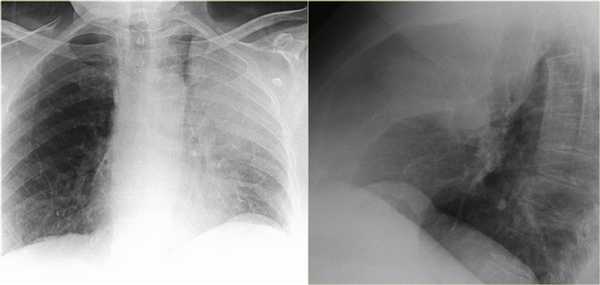

Ателектаз нижней доли левого легкого

На рентгенограмме визуализируются изменения трехгранной формы высокой плотности, расположенные позади тени сердца, что хорошо выявляется на боковом снимке. На боковом снимке при оценке контура диафрагмы спереди назад определяется все менее четко. Исходя из названия раздела напрашивается диагноз — ателектаз нижней доли левого легкого. В норме прозрачность легкого внизу выше, а в нашем случае наоборот (синяя стрелка).

На рентгенограмме органов грудной клетки определяется тотальный ателектаз правого легкого со смещением средостения вправо. На втором снимке представлен тот же пациент, но после лечения. Легкое воздушное и положение средостения в норме. Распространенной причиной тотального ателектаза является неправильно установленная вентиляционная трубка, которая расположена слишком низко и тем самым обтурирует главный бронх.

На ниже представленном снимке представлен пациент с тяжелой бронхопневмонией и тотальным ателектазом. Причиной ателектаза явилось обтурация бронха слизью. После отсасывания мокроты аэрация левого легкого была восстановлена.